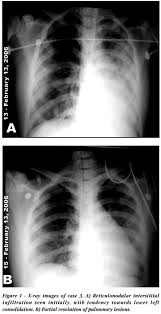

Blood pressure is not something measured off a laboratory result sheet but it is important to monitor in kidney patients as there is a tendency for hypertension to develop in kidney failure. Special medications may be needed to manage this problem should it arise.4. Radiology Tests.

A kidney or abdominal ultrasound is the preferred test for diagnosing kidney failure, but abdominal x-ray, abdominal CT scan, or abdominal MRI can tell if there is a blockage in the urinary tract.